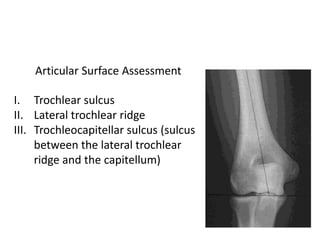

Articular Surface Assessment

I. Trochlear sulcus

II. Lateral trochlear ridge

III. Trochleocapitellar sulcus (sulcus

between the lateral trochlear

ridge and the capitellum)